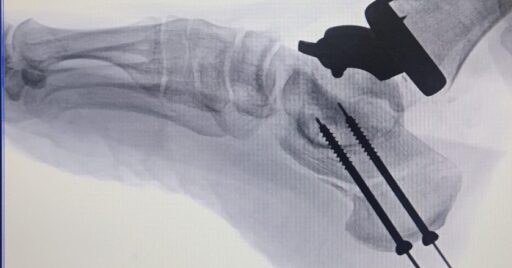

Rescate de pseudartrosis artrodesis de hallux

¿Has escuchado hablar de pseudartrosis y artrodesis de hallux? Estos términos médicos pueden sonar complicados, pero te explicaremos de forma sencilla qué significan y por qué a veces es necesario